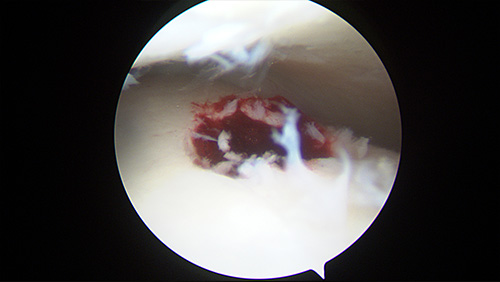

Osteochondral lesions

Description:

A layer of cartilage covers the bones where they meet in the joints, acting as a cushion to allow smooth movement. Osteochondral lesions occur when an area of this cartilage lining is damaged. They can cause pain, clicking, locking, grinding and giving way in the ankle joint.

Treatment:

Mild lesions will likely heal with physiotherapy. More severe lesions may necessitate keyhole surgery.

Stem Cells

Stem cell therapy is a revolutionary advancement in medicine. Some cells in our body, generally extracted from the bone marrow via a needle, have the capacity to regenerate into healthy tissues after these being damaged. In the field of orthopaedics Stem Cells are mainly used in cases of cartilage damage or Osteochondral lesions as an adjunct to help improve the body’s natural healing response. These techniques include the so-called AMIC (Autologous Matrix-Induced Chondrogenesis) to recreate damaged cartilage and MAST (Matrix-Associated Stem Cell Transplantation).